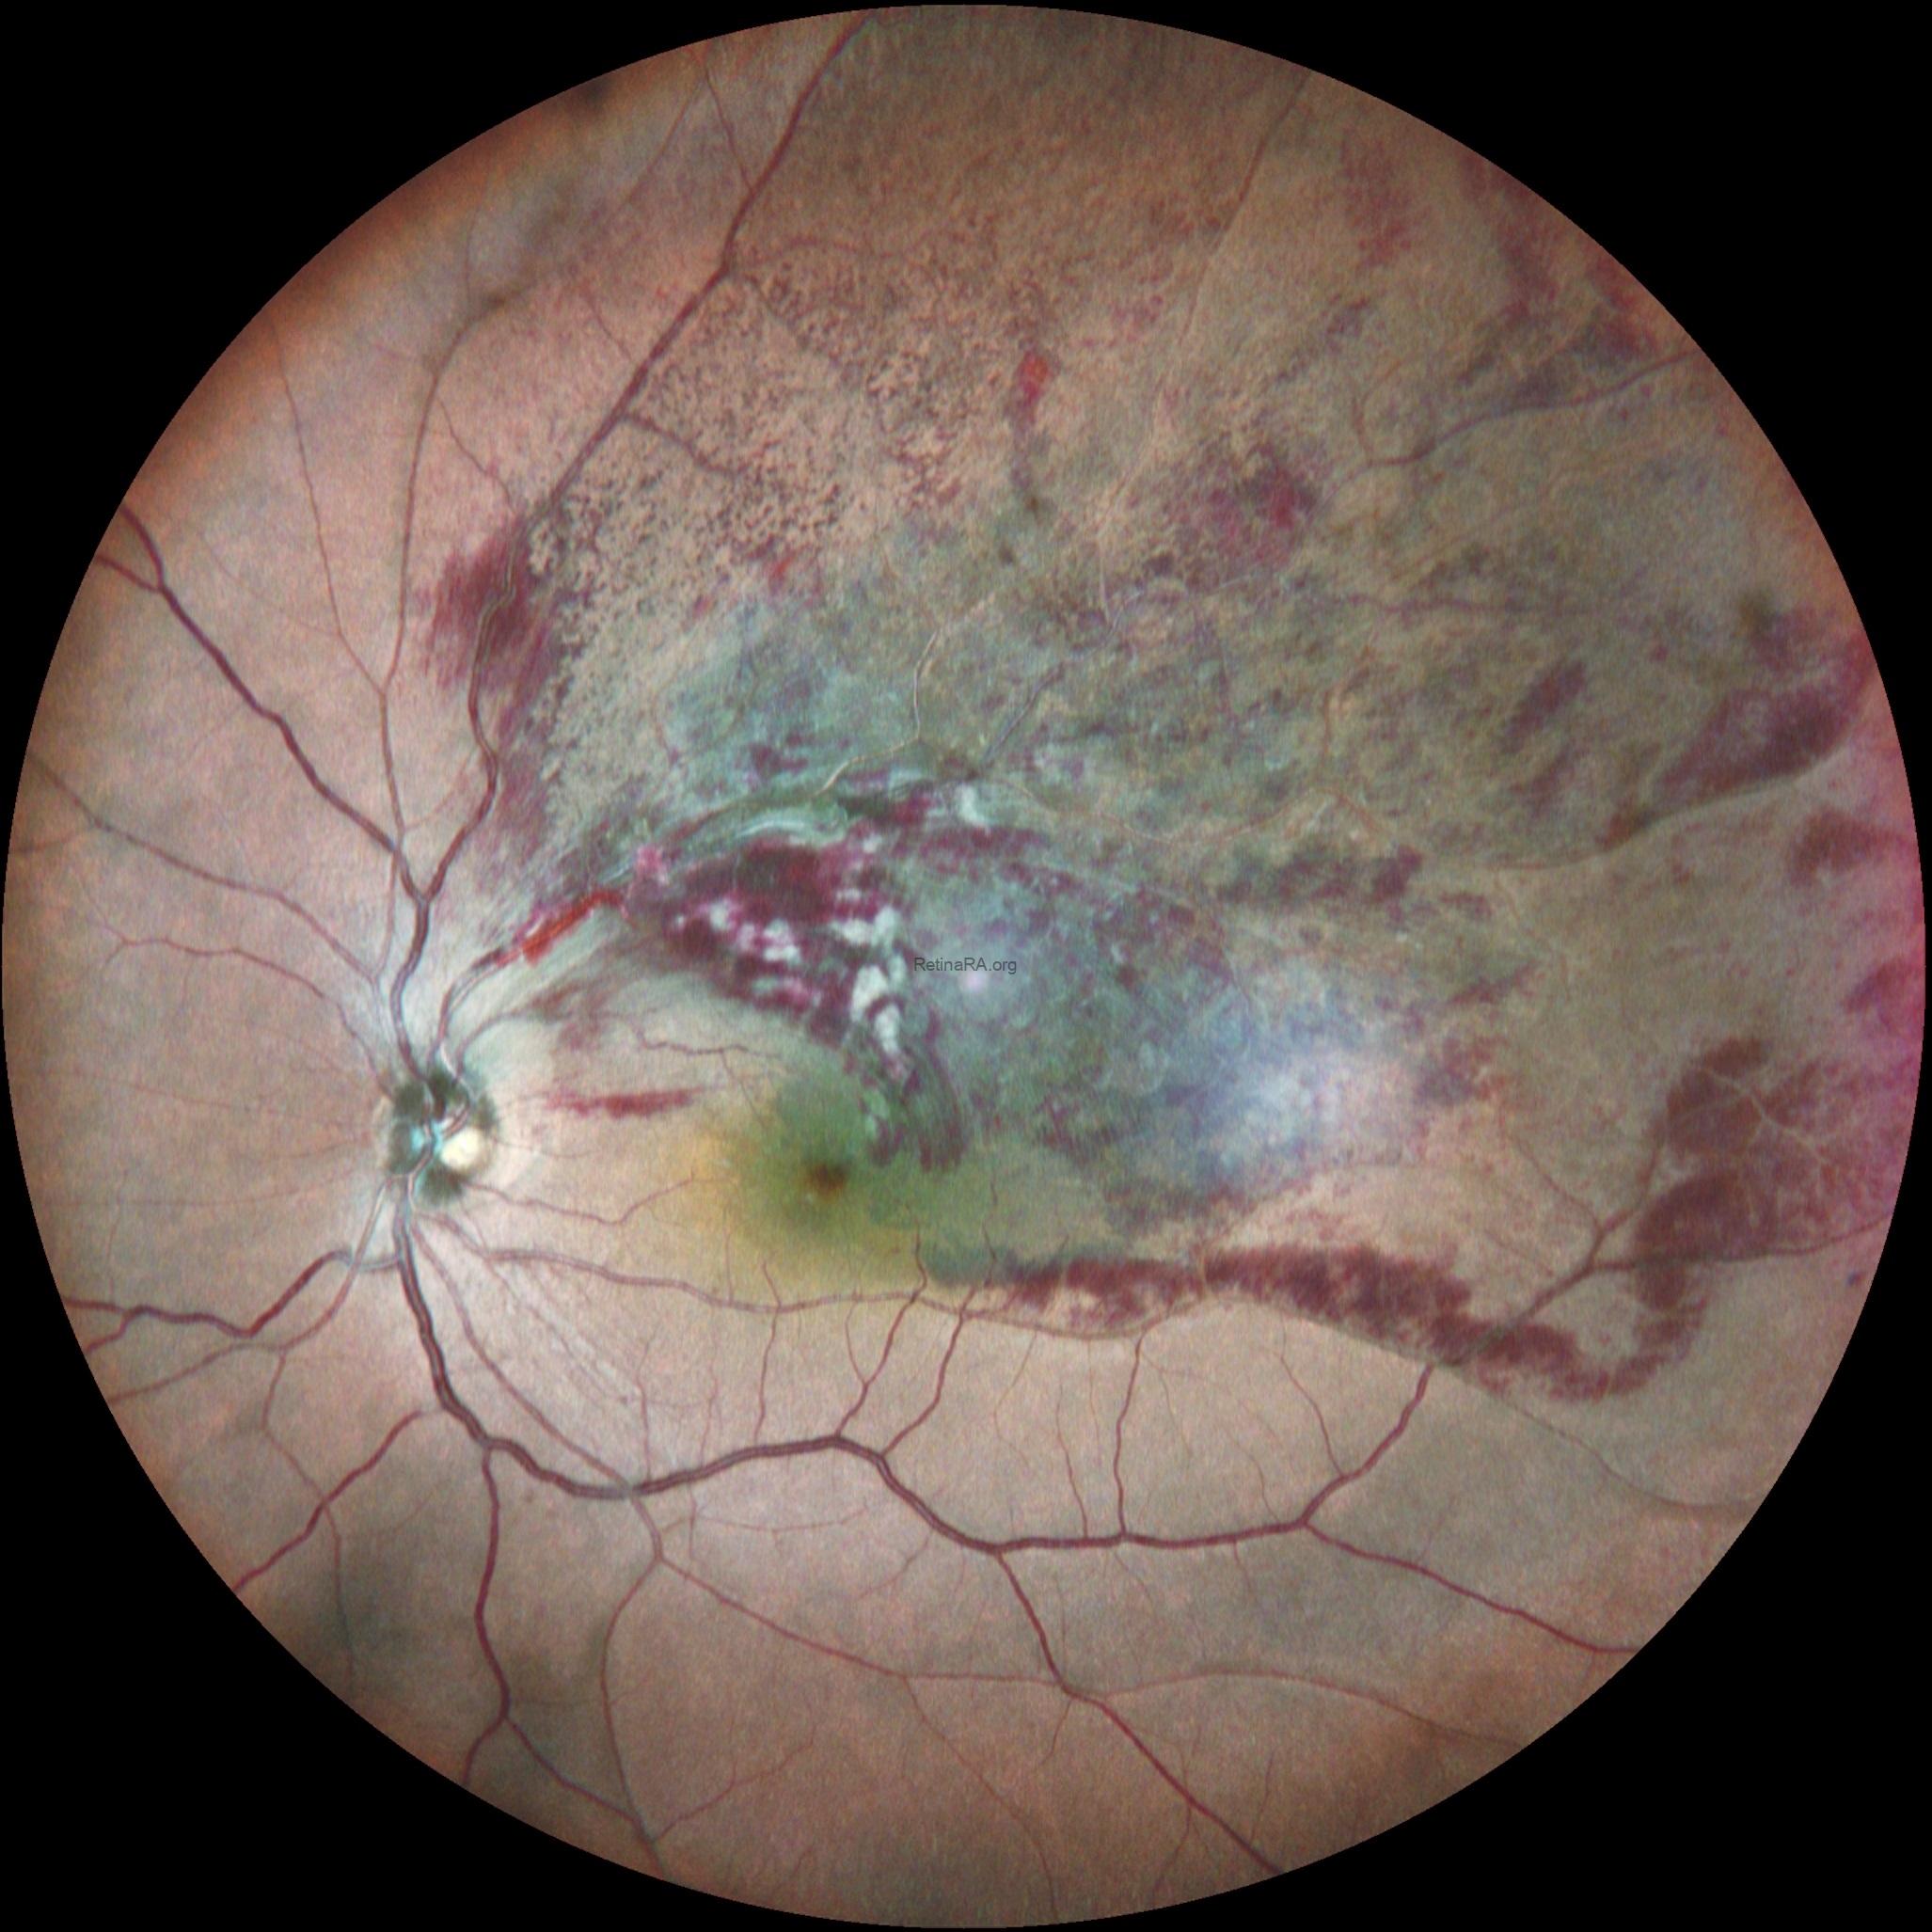

Color fundus photography of the left eye revealed sectoral flame-shaped and blot intraretinal hemorrhages confined to the superotemporal quadrant. Cotton-wool spots were present, and macular edema extending toward the fovea was noted.

Based on the clinical and multimodal imaging findings, a diagnosis of superotemporal branch retinal vein occlusion with secondary macular edema was established. The patient was counseled regarding systemic risk factor control and scheduled for intravitreal anti–vascular endothelial growth factor (anti-VEGF) therapy, with close follow-up planned to monitor anatomical and visual outcomes.